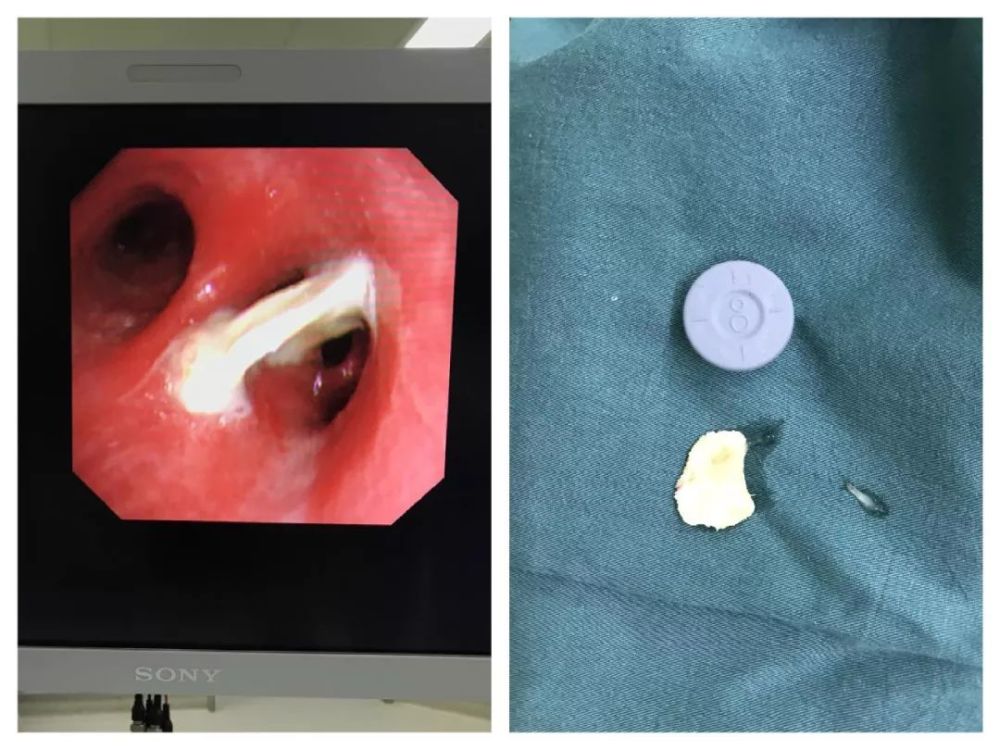

支气管镜下发现异物不完全阻塞左主支气管.

左主支气管内异物取出过程中.